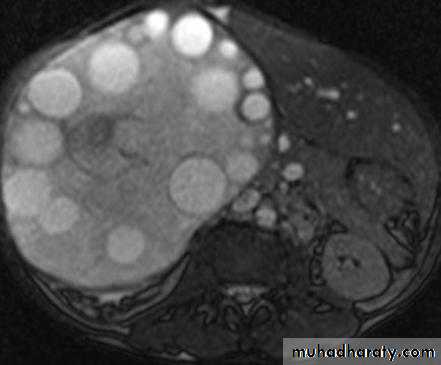

Hydatid cysts may be single or multiple; a few show calcified walls. Daughter cysts may be seen within a main cyst at both US and CT.